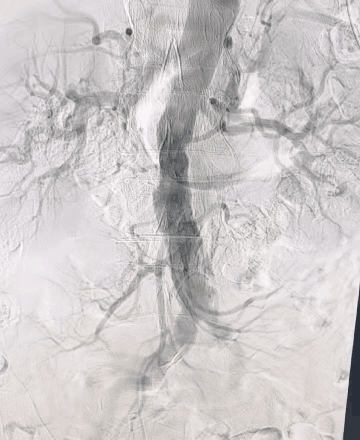

导丝导管配合经左锁骨下动脉选入降主动脉,造影见双肾动脉血流通畅,左髂总动脉局部重度狭窄,左髂外动脉及股腘动脉血流通畅。

动脉长鞘怎么置入桡胜一筹丨吴巍巍主任、赵俊来教授团队:应用Brite Tip RADIANZ长鞘经桡动脉治疗下肢动脉粥样硬化闭塞症一例_https://www.jmylbn.com_新闻资讯_第15张

动脉长鞘怎么置入桡胜一筹丨吴巍巍主任、赵俊来教授团队:应用Brite Tip RADIANZ长鞘经桡动脉治疗下肢动脉粥样硬化闭塞症一例_https://www.jmylbn.com_新闻资讯_第16张